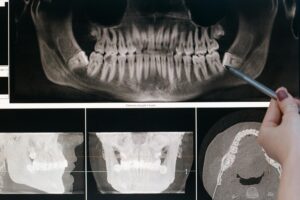

Difficoltà nell’aprire e chiudere la bocca? Necessaria una visita gnatologica

Mal di testa, mal di schiena, acufeni, difficoltà nell’aprire e chiudere la bocca possono talvolta vedere direttamente coinvolti i denti. Quando ad esempio l’arcata dentale superiore non è perfettamente allineata con l’arcata dentale inferiore, si può andare incontro a diverse problematiche. Grazie a un’approfondita visita gnatologica si rende, in questo come tanti altri casi, necessaria. […]